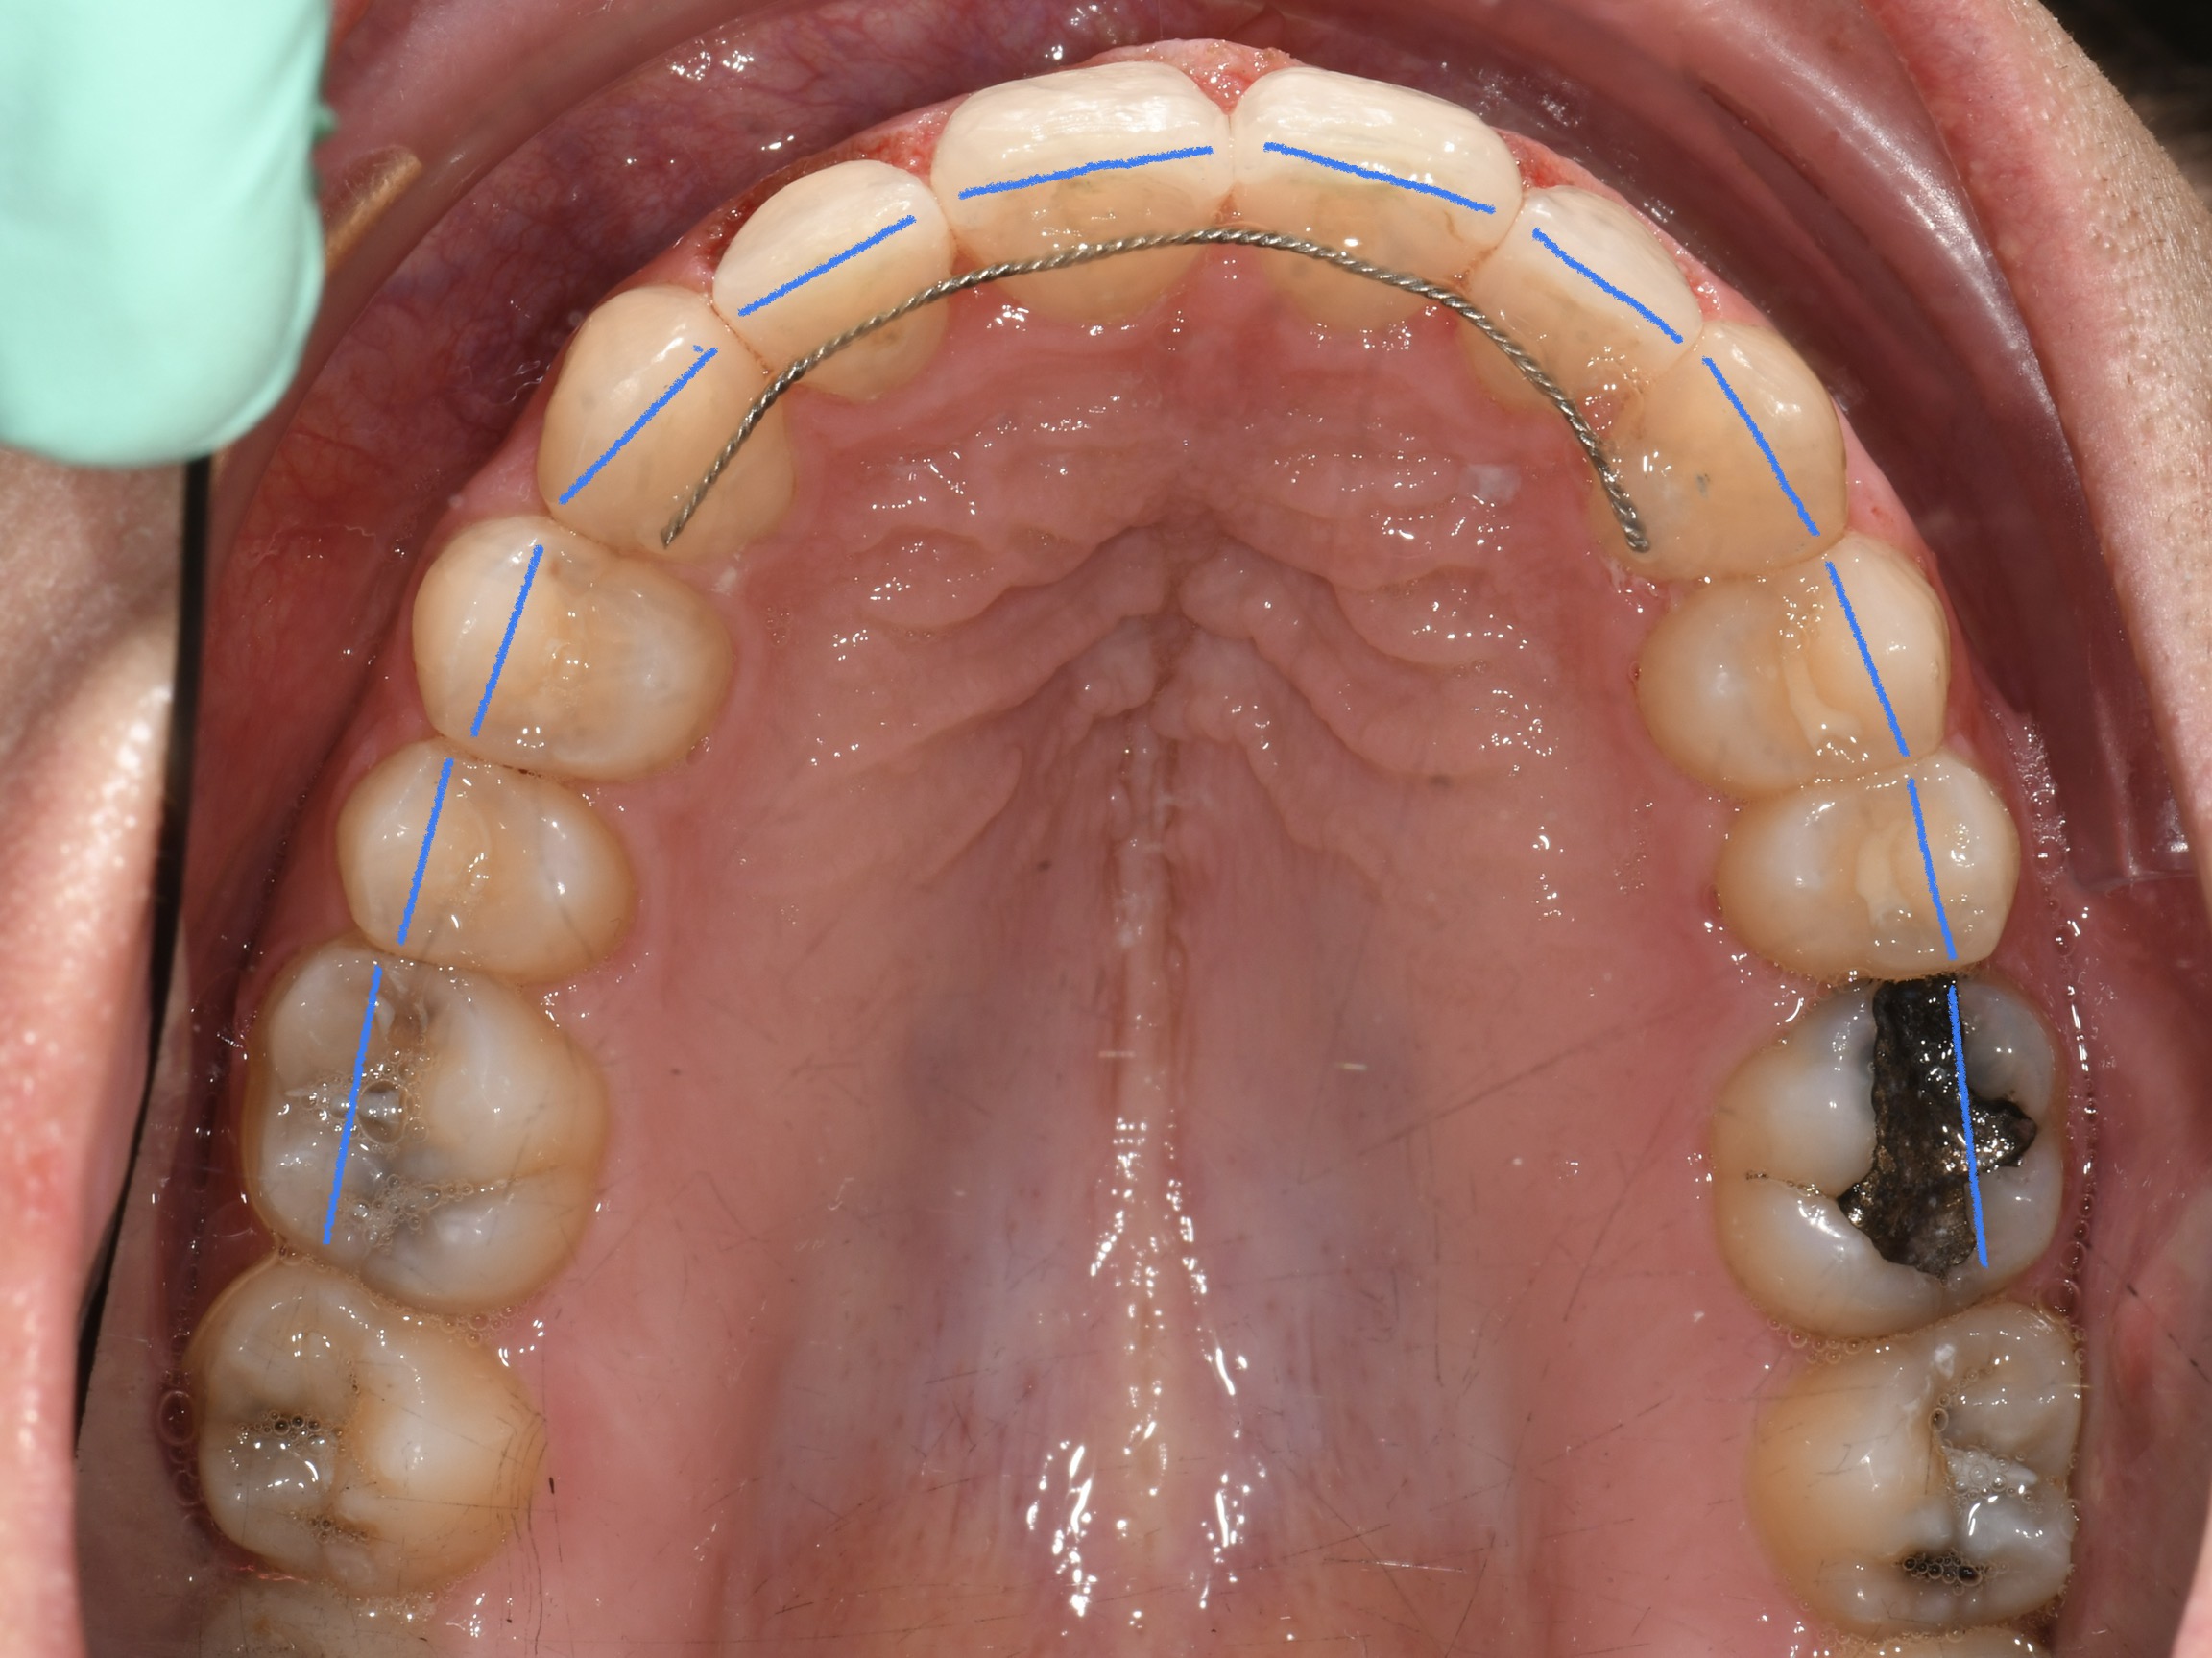

Az elmúlt évekből rengeteg szakmai referenciát tudnánk bemutatni, amelyek különböző fogszabályozási problémákat oldottak meg. Válogatva a több száz esetből, ezen az oldalon olyan képeket, információkat igyekeztünk bemutatni, amelyeknek a segítségével a jövőbeni pácienseinknek azt tudjuk üzenni: A Te fogsorod is lehet gyönyörű!

(Képeket a Pácienseink külön írásos beleegyezésével mutatjuk be!)